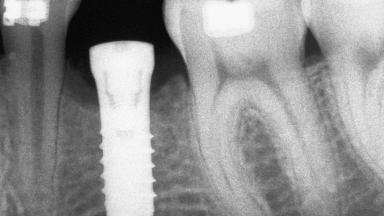

An 18-year-old man was referred for implant therapy in the posterior mandible to the Department of Oral Surgery and Stomatology (University of Bern, Switzerland). He was healthy and did not smoke. Tooth 35 was congenitally missing, involving a single-tooth edentulous space that offered an adequate mesiodistal dimension for implant placement but exhibited a typical pattern of buccal flattening. A panoramic radiograph was obtained, which revealed a sufficient vertical bone height above the mandibular canal and a normal bone structure in the edentulous area.

Bone Augmentation Horizontal|Staged

Augmentation Materials Autogenous chips|Autogenous block(s)|Xenogenous|Membrane

Bone Volume Deficient horizontally, requiring prior grafting